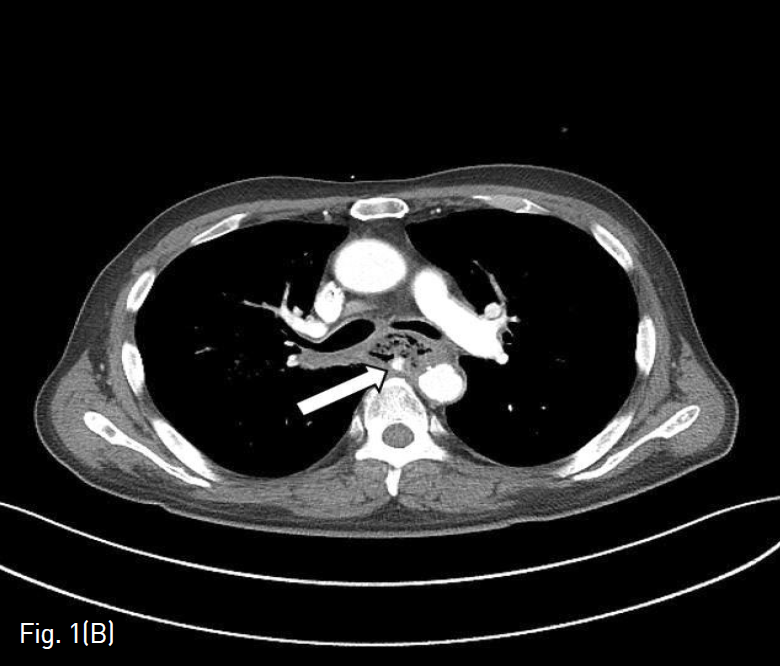

응급으로 시행한 조영증강 흉부 컴퓨터단층촬영에서 폐 우상엽의 중앙 부분과 내측에 공동을 동반한 폐렴이 있었다. 식도 중부의 후벽에 조영 증강되는 가성동맥류가 있었으며 대동맥에서 가성동맥류로 연결되는 대동맥식도루가 보였다 (Fig. 1B). 흉부 컴퓨터단층촬영에서 식도 내강으로의 조영제의 명확한 유출은 보이지않았으나, 해당 위치에서 출혈이 있는 것으로 판단하고 응급으로 혈관 내 치료가 의뢰되었다(Fig. 1C).

(B-C) On chest CT performed in emergency, pseudoaneurysm and aorto-esophageal fistula are seen in the posterior wall of the esophagus (arrows).